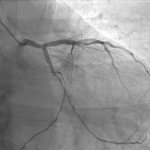

Attacks of VSD are always accompanied by “signals” from the blood vessels and the heart. A syndrome that is harmless at first glance, if not in a timely manner , can lead to serious disruptions in the functioning of the body:

• the appearance of regular panic attacks with a consistently reduced emotional background;

• hypoxia (oxygen starvation) and deterioration of cerebral circulation;

• atherosclerosis, hypertension, varicose veins, angina, heart attack, stroke and other pathologies of the cardiovascular system.

The “drops” in blood pressure that patients with VSD experience when drinking alcohol overload the heart and blood vessels. Over time, wear and tear of the cardiovascular system can trigger a heart attack or stroke with minimal physical exertion.